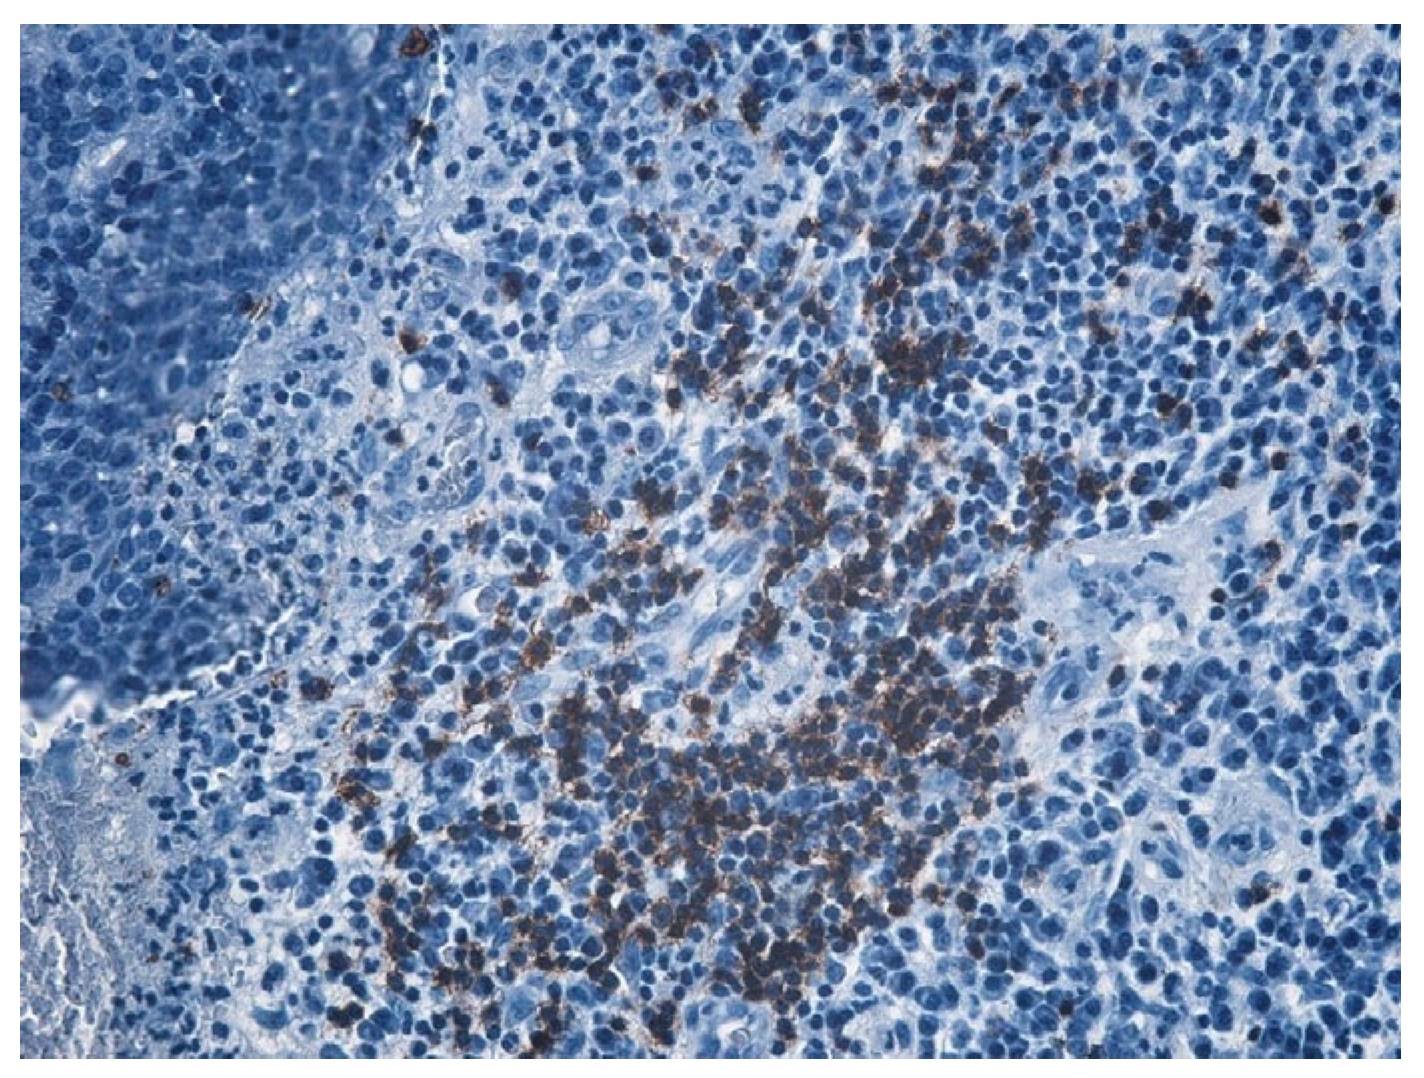

| Histopathologic Aspects | Number of Patients |

|---|---|

| Cholesteatom | 276 |

| Polip | 180 |

| Tympanic membrane mucosa chamber, epithelium with apocrine-like cells, and chronic inflammatory infiltrate | 128 |

| Cell Types | Percentage |

| Lymphocytes T | 42.55% |

| Lymphocytes B | 31.45% |

| Macrophages | 26.00% |